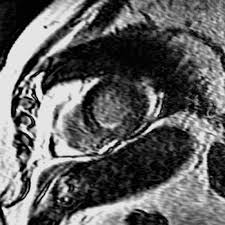

The mri myocarditis protocol encompasses a set of different mri sequences for the cardiac assessment in case of suspected myocardial inflammation. Pdf | on jan 1, 2013, m gutberlet and others published mrt bei myokarditis | find, read and cite all the research you need on researchgate Myocarditis, also known as inflammatory cardiomyopathy, is inflammation of the heart muscle.symptoms can include shortness of breath, chest pain, decreased ability to exercise, and an irregular heartbeat. This article aims to frame a general concept of a cardiac mri protocol in the above setting. Exactly how many people are affected is hard to know because it often has no symptoms.

Stellenwert des late gadolinium enhancement im mrt bei myokarditis february 2021 conference: Thomas alexander ochtrop and dr matt a. Various mri parameters are available which have different accuracies. Myocarditis can affect your heart muscle and your heart's electrical system, reducing your heart's ability to pump and causing rapid or abnormal heart rhythms (arrhythmias). Eine myokarditis kann folge einer nicht ausgeheilten viralen oder sonstigen infektion oder autoimmun, autoentzündlich, toxisch oder allergisch bedingt sein. Myocarditis myocarditis is an inflammation of the heart muscle (myocardium). Heilt in den meisten fällen folgenlos aus, es gibt jedoch auch schwerste verläufe mit komplikationen bis hin zum plötzlichen herztod. 23 january 2013 | der radiologe, vol. Rest and reducing the workload on your heart is an important part of recovery. Explore mayo clinic studies testing new treatments, interventions and tests as a means to prevent, detect, treat or manage this condition. In der mehrzahl der erkrankungen liegt eine virusinfektion mit zerstörung von kardiomyozyten in kombination mit einer. Complications may include heart failure due to dilated cardiomyopathy or cardiac arrest. Myocarditis, also known as inflammatory cardiomyopathy, is inflammation of the heart muscle.symptoms can include shortness of breath, chest pain, decreased ability to exercise, and an irregular heartbeat.

The duration of problems can vary from hours to months. Thomas alexander ochtrop and dr matt a. Prerequisites for this are noninvasive and invasive biomarkers including endomyocardial biopsy and polymerase chain reaction on cardiotropic agents. Request pdf | myokarditis in der kardialen mrt myocarditis in cardiovascular magnetic resonance | die myokarditis stellt eine entzündliche erkrankung des herzmuskels dar, die verschiedenste. This article aims to frame a general concept of a cardiac mri protocol in the above setting. For myocarditis and inflammatory cardiomyopathy, an etiologically driven treatment is today the best option beyond heart failure therapy. 23 january 2013 | der radiologe, vol. Eine myokarditis kann folge einer nicht ausgeheilten viralen oder sonstigen infektion oder autoimmun, autoentzündlich, toxisch oder allergisch bedingt sein. Stellenwert des late gadolinium enhancement im mrt bei myokarditis february 2021 conference: Die myokarditis ist als ein inflammatorischer prozess des myokards definiert. Acute coronary syndrome (acs) is frequent and prognostically relevant. In der mehrzahl der erkrankungen liegt eine virusinfektion mit zerstörung von kardiomyozyten in kombination mit einer. 23 january 2013 | der radiologe, vol.